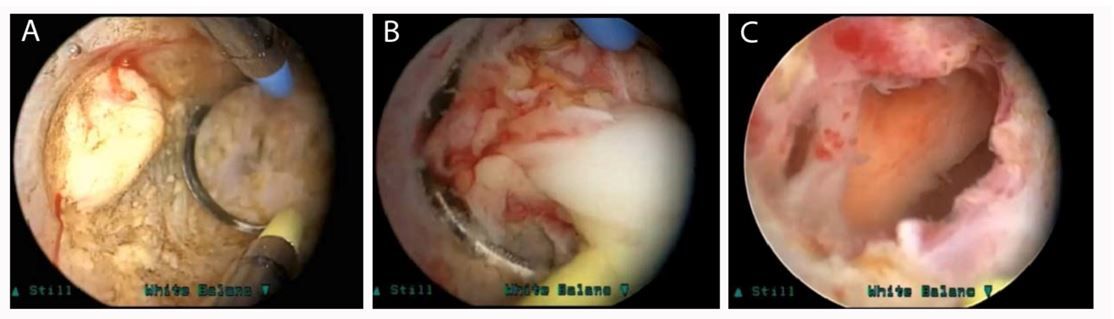

- Nội soi xẻ ổ abscess (Transurethral incision over abcess - TUI)

- Nội soi phá ổ abscess(Transurethral deroofing of abscess cavity – TUD)

Hình 3: chọc hút ổ abcess dưới hướng dẫn siêu âm qua ngã trực tràng

Hình 4: nội soi phá ổ abcess

Hiện tại vẫn chưa có bằng chứng hay khuyến cáo nào cho việc lựa chọn phương pháp dẫn lưu ổ abscess, quyết định thường dựa trên kinh nghiệm và sự ưa thích của phẫu thuật viên. Chọc hút/đặt dẫn lưu qua ngã trực tràng dưới hướng dẫn siêu âm là thủ thuật nhẹ nhàng tuy nhiên tỷ lệ tái phát 15 – 33%. Những tổn thương quá lớn hay chọc hút/dẫn lưu không hiệu quả cần được nội soi để dẫn lưu ổ abcess. Các phương pháp TUI và TUD có lợi điểm là can thiệp tối thiểu nên hạn chế được các biến chứng liên quan đến cắt đốt nội soi tuyến tiền liệt như chảy máu, xuất tinh ngược và tiểu không kiểm soát. Bất lợi lớn nhất của 2 phương pháp trên là nguy cơ dẫn lưu không hoàn toàn ổ abscess.